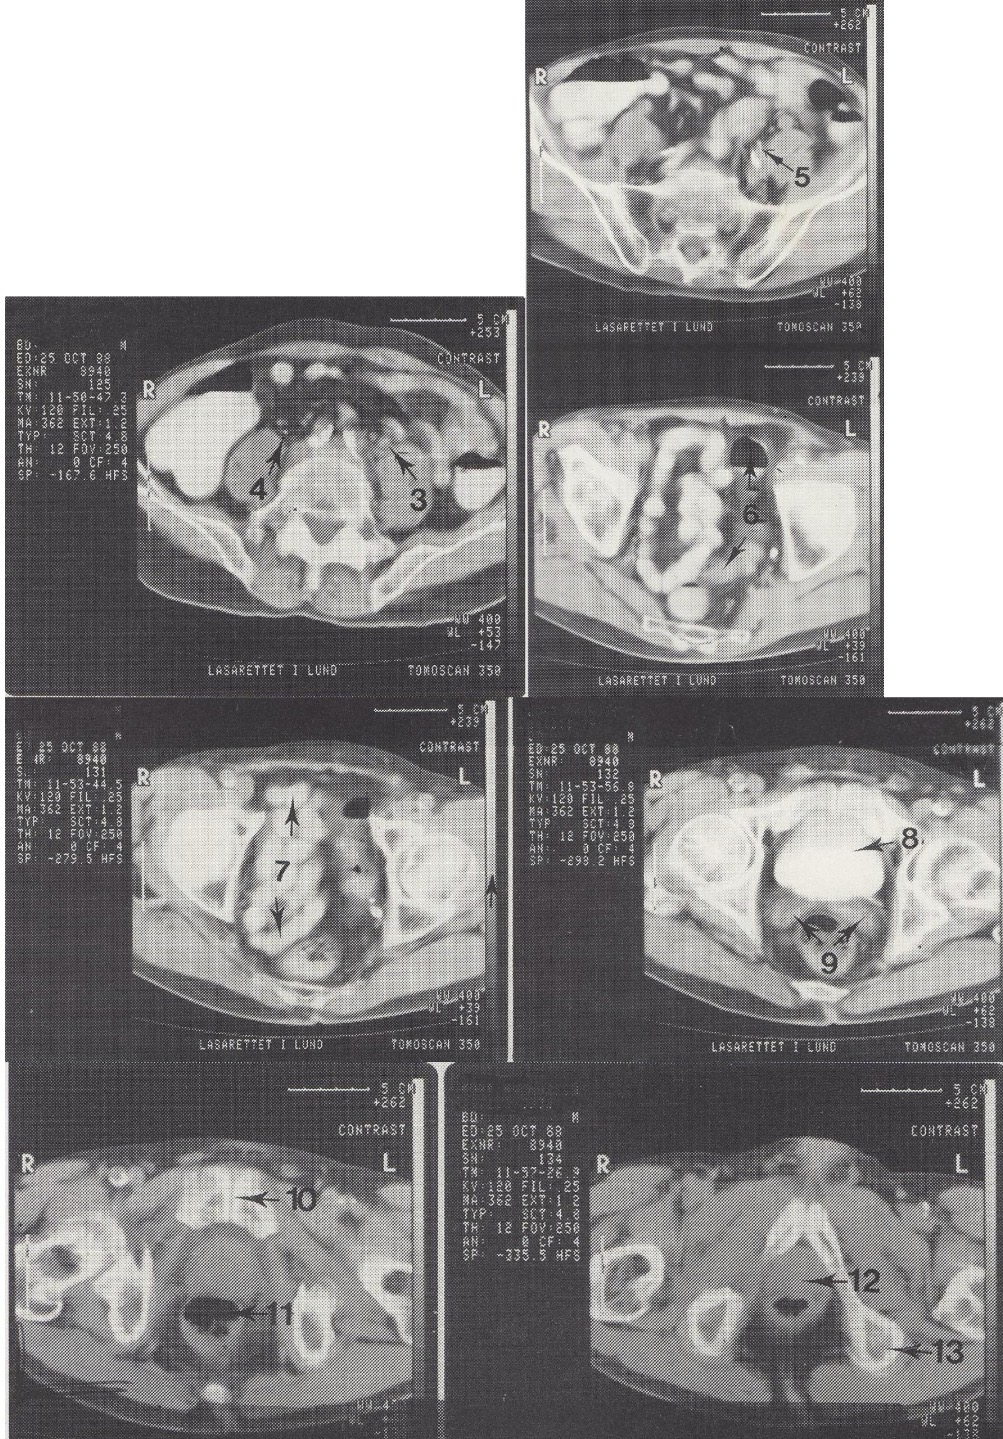

5

A. iliaca interna sin. (kairioji vidinė klubo arterija)

6

Colon sigmoideum (riestinė žarna)

7

Ileum kilpos dubenyje (tuščiosios žarnos kilpos)

8

Vesica urinaria (šlapimo pūslė, užpildyta kontrastu)

9

Vesiculae seminales (sėklinės pūslelės)

10

Symphysis pubica (gaktinė sąvarža)

11

Rectum (tiesioji žarna)

12

Prostata (priešinė liauka)

13

Tuber ossis ischii sin. (kairysis sėdimasis gumburas)

Metodika

KT pjūviai nuo juosmens slankstelių iki gaktinės sąvaržos apačios. Suleistas intraveninis kontrastas (išryškina šlapimo takus) ir išgertas kontrastas (išryškina žarnyną).